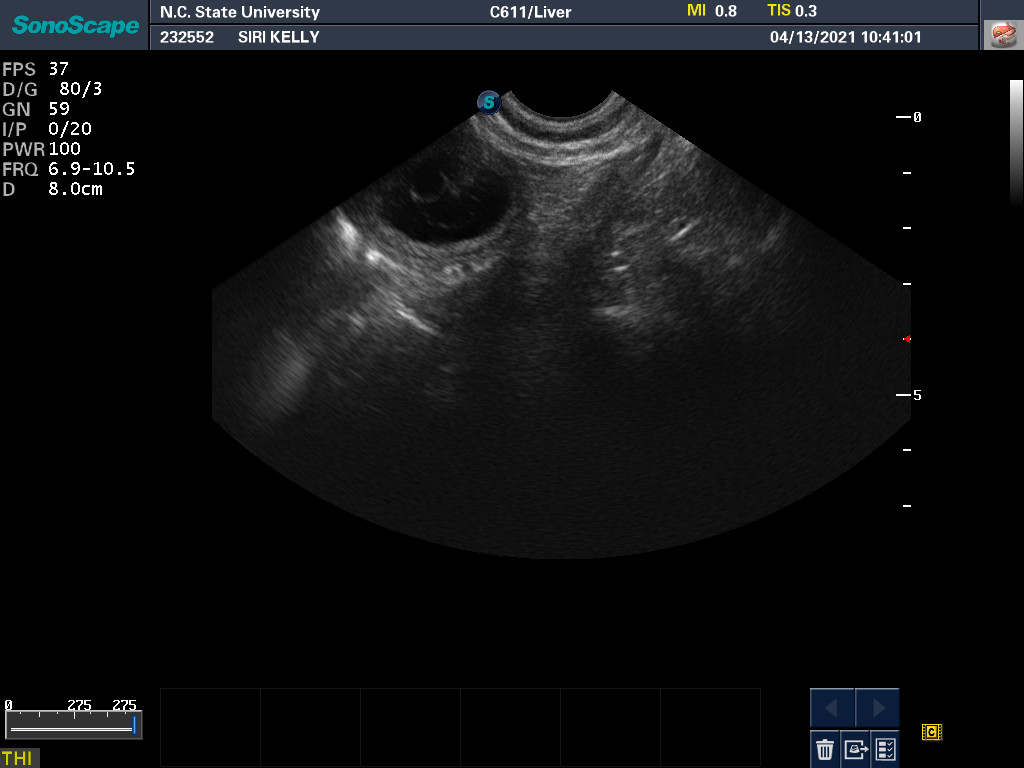

13 Apr

Ultrasound today by the theriogenology (reproduction) veterinarians at NC State University showed that Siri is pregnant with possibly four puppies. (It can be difficult to accurately count puppies using ultrasound.)

If all goes well, puppies are due around 18 May.